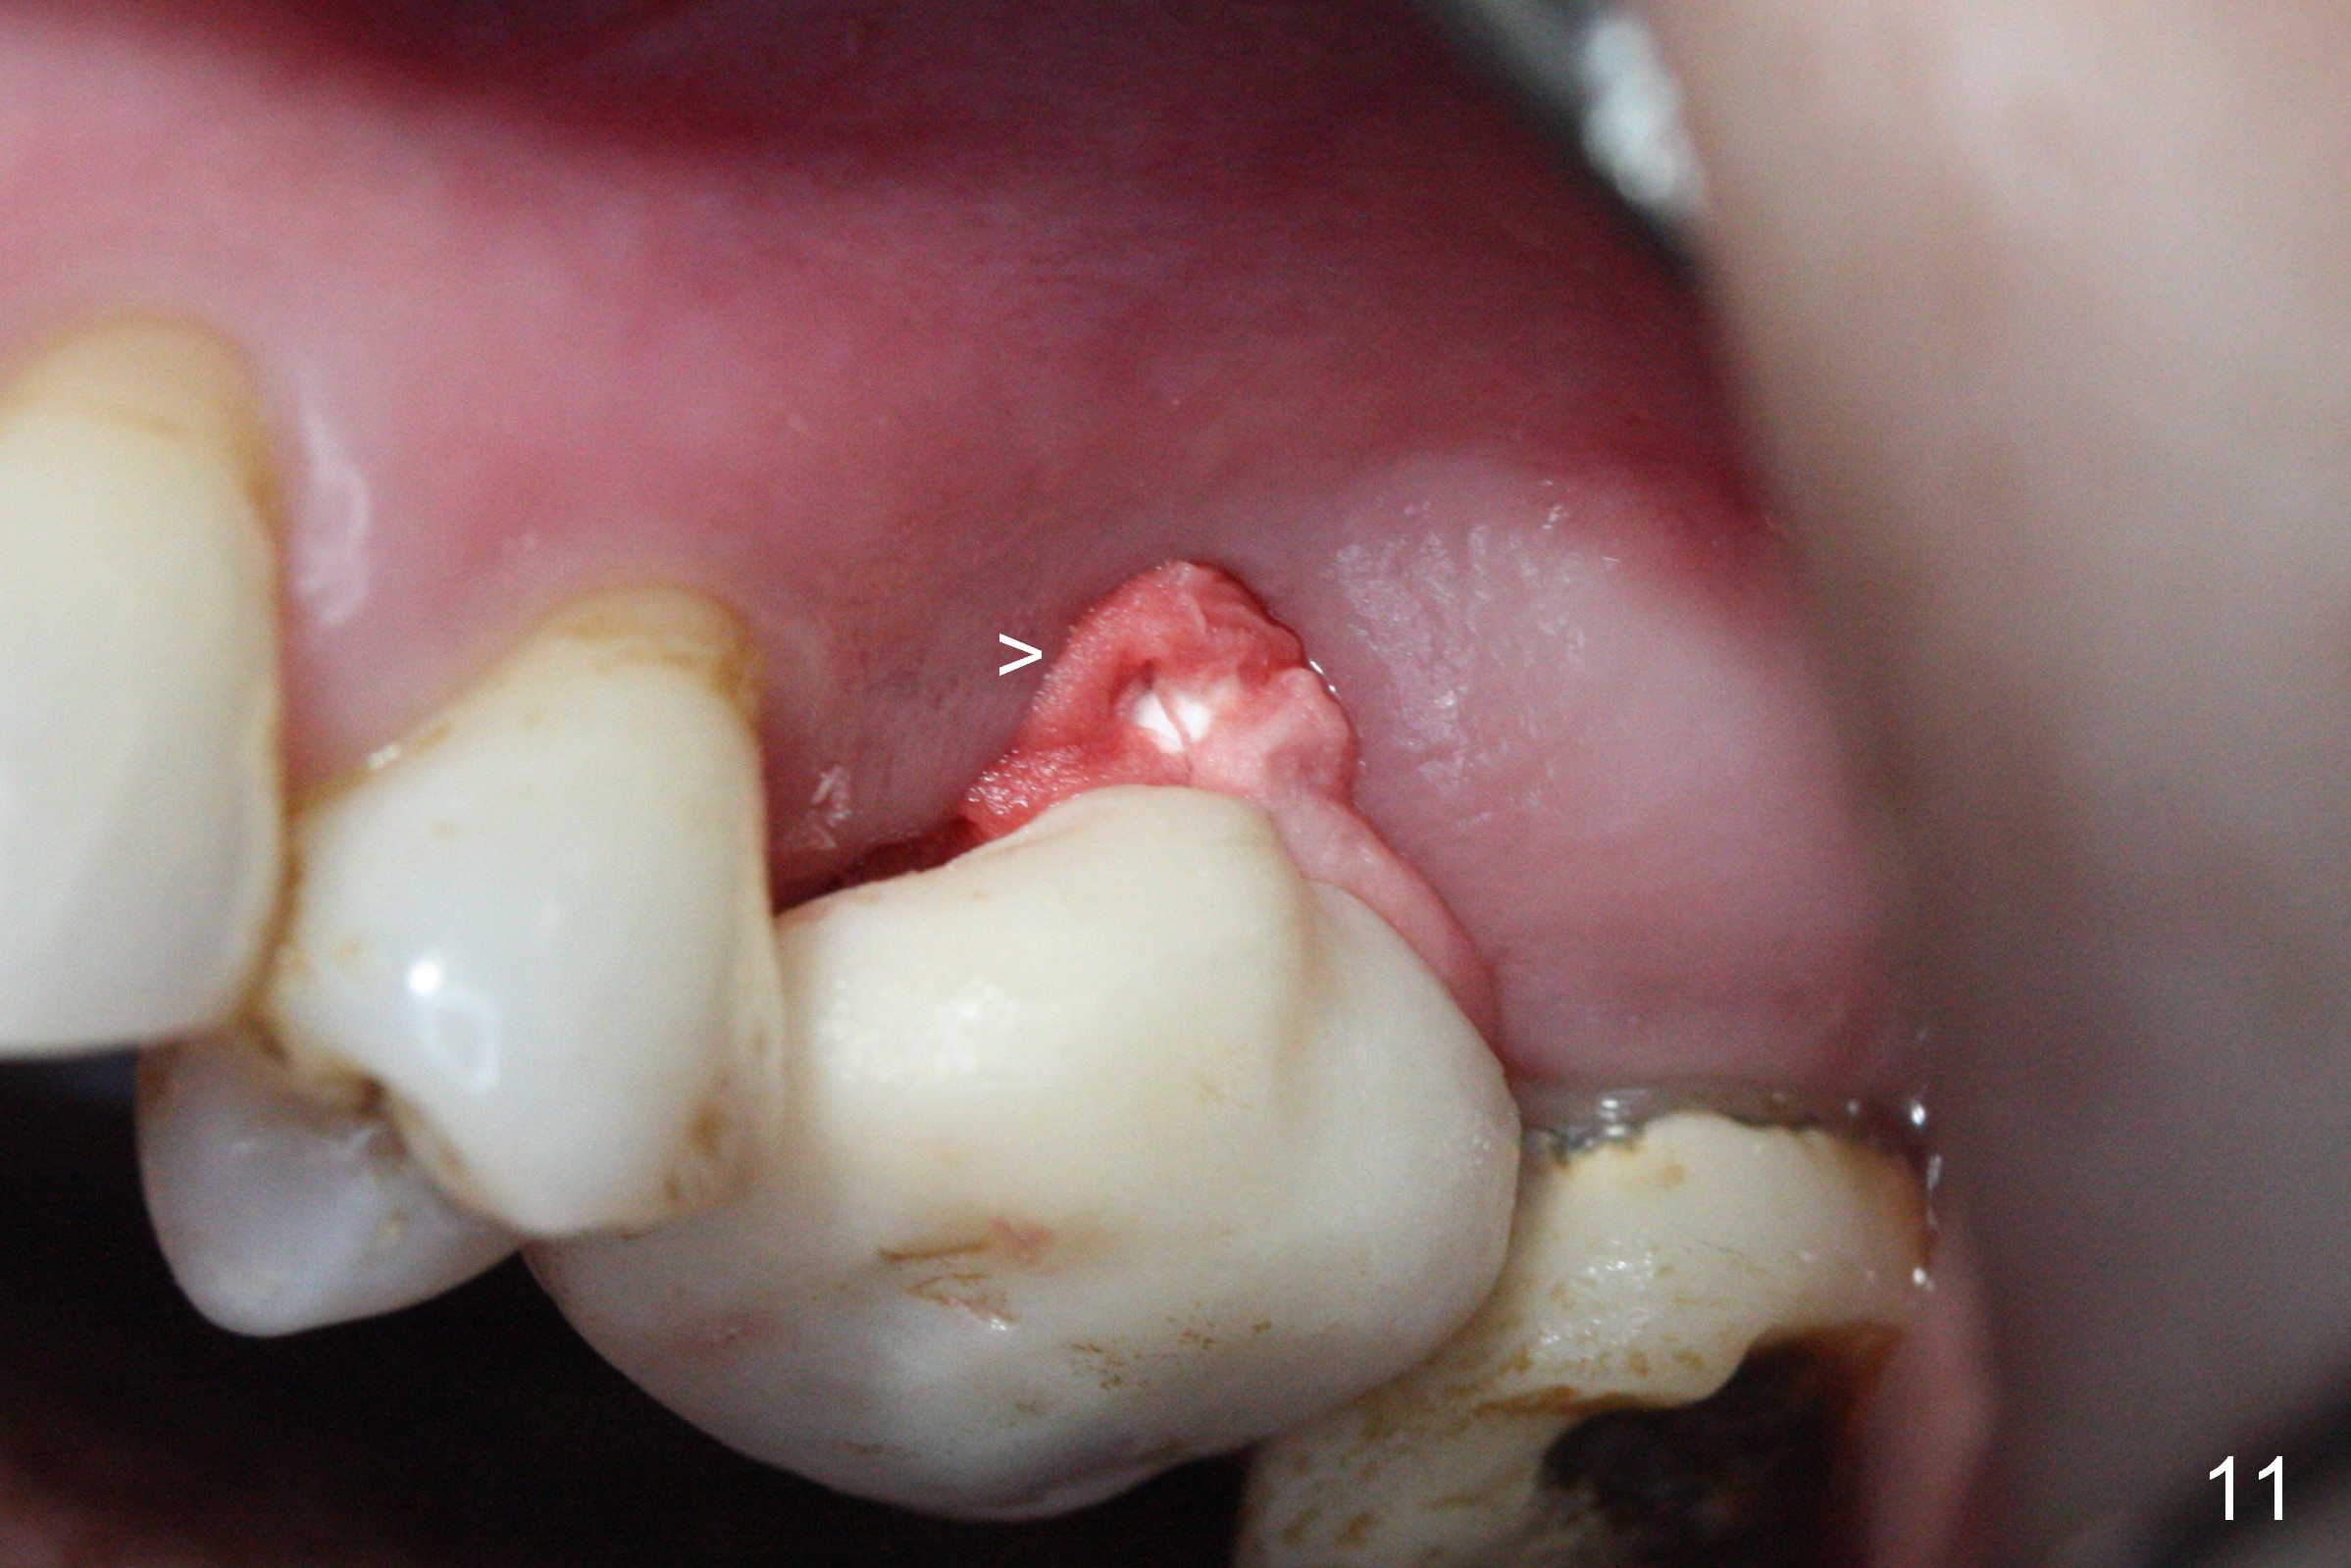

There is abundant subgingival calculus on the surfaces of the extracted tooth at #14 (Fig.1: P: palatal; MB: mesiobuccal), corresponding to the large empty socket (Fig.2 without septal bone, the buccal plate being low). Osteotomy is established palatally with Magic Expander (ME) 3.0 mm for ~ 3 mm deep (Fig.3,4) with minimal stability so that it moves during X-ray taking (Fig.4). Since the bone is dense, Magic drill 4.3 mm is used after application of ME 3.8 and 4.3 mm to complete sinus lift (Fig.5 (panoramic X-ray)). A 5x11 mm implant is placed with ~ 30 Ncm, followed by insertion of 6.5x4(3) mm Hexa abutment, bone graft and collagen membrane (Fig.6). The latter is kept in placed with an immediate provisional with clearance from the opposing dentition (Fig.7 *). Between the 1st and 3rd weeks postop, the buccal gingiva recedes with loss of bone graft (Fig.8 <) and implant thread exposure (Fig.9 * (A: abutment)). After inducing hemorrhage, allograft is placed (Fig.10 >), followed by collagen dressing (Fig.11 >). The wound closes by adding new acrylic (Fig.12 *). Thirteen days later, food is trapped in the buccal gap (Fig.13 ^). It appears that the provisional does not help wound healing. The provisional and abutment are removed; incorporating bone graft (Fig.14 *) and the implant are exposed. After placing collagen plug against the bone graft and implant, the wound is closed by periodontal dressing.